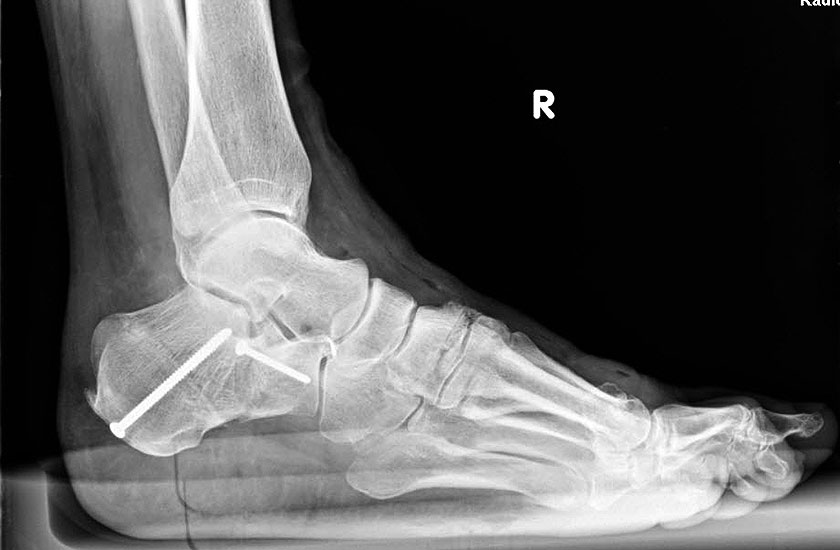

Radiologisches Beispiel einer fixierten Planovalgus Deformität Stadium III, 51 jähriger Patient. Stehendes präoperatives Röntgenbild und 1 Jahr postoperatives Röntgenbild des Fußes seitlich. Die Korrektur der Deformität umfaßte eine leicht korrigierende U

Abbildung 12

Im Stadium III der Tibialis posterior Sehneninsuffizienz bei fixierter Deformität und/oder erheblich eingeschränkter Inversion im USG aber stabilen und flexiblen Chopart-Gelenk und weniger als 10° fixierter Vorfußsupination eine in-situ oder leicht korrigierende USG-Arthrodese indiziert. Der Vorteil einer isolierten USG-Arthrodese gegenüber einer Triple- oder Double-Arthrodese ist die verbleibende, funktionell wichtige Beweglichkeit in der Chopart-Gelenkreihe. Um einem persistierenden fibulocalcanearem Impingement sicher vorzubeugen, sollte die USG-Arthrodese in maximal 5° Valgus- oder sogar Neutralposition erfolgen. Zur Prophylaxe eines Rezidivs wird die USG-Arthrodese zudem häufig mit einer medialisierende Tuber calcanei Osteotomie und / oder einem FDL-Transfer kombiniert (Abb. 12).